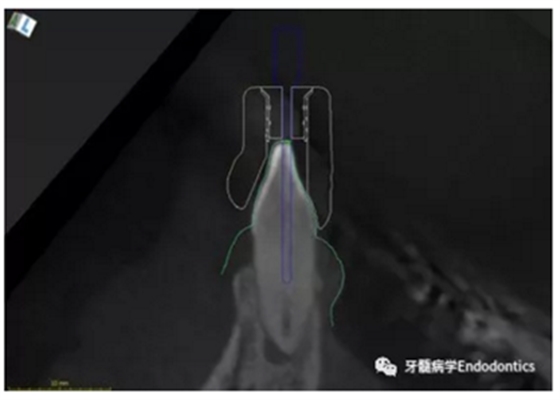

31、41叩痛明顯,牙冠變色(圖1)。溫度和牙髓電活力測(cè)試無(wú)反應(yīng)。兩張從不同角度拍攝的x線(xiàn)片顯示,相對(duì)于側(cè)切牙,雙側(cè)下中切牙都有嚴(yán)重的根管鈣化(圖2)。41有明顯根尖周暗影,31根尖周暗影不明顯。為進(jìn)一步證實(shí)31是否存在根尖周病變,同時(shí)精細(xì)觀(guān)察31、41的復(fù)雜結(jié)構(gòu),根據(jù)歐洲牙髓病學(xué)會(huì)CBCT應(yīng)用指南(2014),對(duì)患牙拍攝小視野、高分辨率CBCT。CBCT影像證實(shí)31、41均伴有根尖周炎和嚴(yán)重的根管鈣化(圖3)。距離根尖4mm可見(jiàn)根管影像。 由于患牙根管解剖結(jié)構(gòu)較為復(fù)雜,筆者決定使用特殊設(shè)計(jì)的微型鉆頭(直徑0.85mm)進(jìn)行“數(shù)字化導(dǎo)航牙髓治療”。 因此對(duì)下頜進(jìn)行口內(nèi)掃描(圖4)。用coDiagnostixTM軟件(Dental Wings Inc.,Montreal,Canada)將CBCT和口內(nèi)掃描的數(shù)據(jù)進(jìn)行處理,該軟件主要用于引導(dǎo)種植。通過(guò)該軟件對(duì)兩個(gè)掃描圖像進(jìn)行疊加后,虛擬鉆頭尖端沿牙長(zhǎng)軸對(duì)準(zhǔn)根管下段可見(jiàn)部分(圖5)。三維檢查虛擬鉆的正確位置。

圖5.虛擬設(shè)計(jì)的微創(chuàng)根管入路。虛擬鉆針的尖端能到達(dá)鈣化根管X線(xiàn)影像中的可見(jiàn)部分。